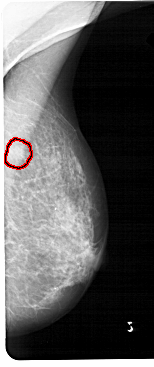

A_1473_1.RIGHT_CC

RIGHT_CC LINES 4636 PIXELS_PER_LINE 2116 BITS_PER_PIXEL 12 RESOLUTION 43.5 OVERLAY

FILE: A_1473_1.RIGHT_CC.OVERLAY

TOTAL_ABNORMALITIES 1

ABNORMALITY 1

LESION_TYPE MASS SHAPE IRREGULAR MARGINS ILL_DEFINED

ASSESSMENT 4

SUBTLETY 3

PATHOLOGY BENIGN

TOTAL_OUTLINES 1

BOUNDARY